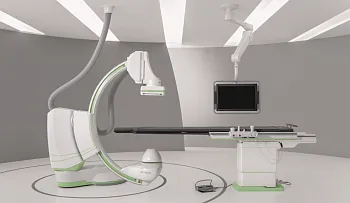

Выгодные комплекты для анестезиологии и реанимации

Официальный дистрибьютор GE HealthСare с 2007 года

Каталог